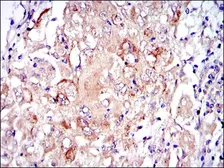

Images